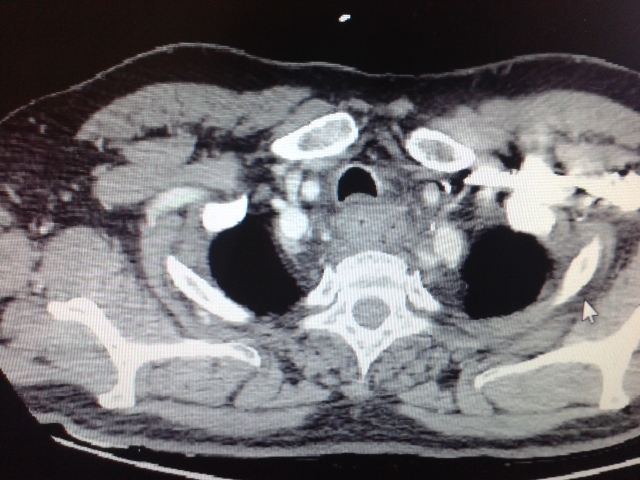

A questo punto il quadro diventa più chiaro… odinofagia, disfagia, febbre, dolore toracico, l’anatra, l’osso appuntito, la lacerazione esofagea … chiediamo subito una TAC collo – torace: “..a livello dello stretto toracico superiore risulta ispessita con scarsa definizione la parete esterna esofagea con soffusione del grasso circostante e presenza di tre bolle aeree periferiche…”.